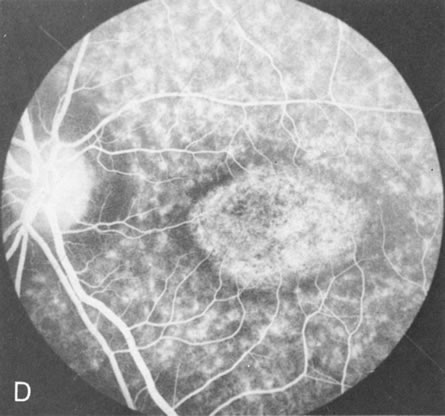

Fig. 4. Choroideremia and choroideremia carrier. A. The choroidal atrophy in this affected male is not apparent in the fundus. B. However, the angiogram shows diffuse atrophy of the choriocapillaris with persistent visualization of the larger choroidal vessels. C. This carrier female has peripapillary choroidal atrophy and diffuse pigment mottling. D. The patchy areas of focal choroidal atrophy that occasionally occurs in carriers is evident on angiography.

The typical carrier female, with focal or diffuse pigment mottling, does not show choroidal atrophy. However, a few carrier females have a more severe form with focal areas of choroidal atrophy. The presence of these areas, and possible progression, can be documented by FA (Fig. 4C and D). These carriers exhibit a mosaicism, which is explained by the Lyon hypothesis of random X-chromosome inactivation.